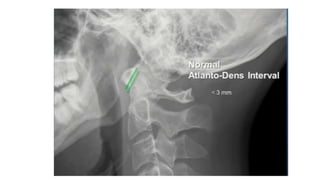

• #33 Basion dense interval <9.5mm

• #34 For true jeff Force hits the vertex of the head, go down through the occ condyles land on c1 and drive c1 to sides and disperse the fragments radially